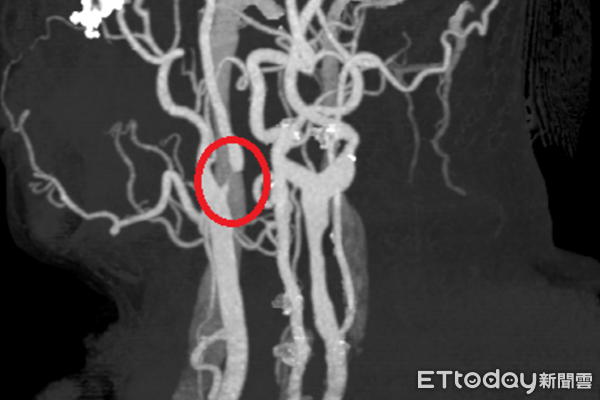

▲頸動脈狹窄影像圖。(圖/衛福部南投醫院提供,下同)

50歲林姓男子近日因不時感到頭暈、左邊手腳麻而就醫檢查,經神經內科醫師初步安排電腦斷層檢查,雖未發現明顯中風跡象,但基於臨床警覺,進一步安排頸動脈超音波檢查,結果發現內頸動脈已有狹窄情形,隨即收治住院觀察,並轉介神經外科醫師接受內頸動脈血管成形術(氣球擴張合併支架置放),成功改善腦部血流,術後恢復良好、已康復出院。

衛福部南投醫院神經外科醫師陳奕安指出,頸動脈狹窄是導致缺血性中風的重要原因之一,早期症狀常不明顯,或僅表現為短暫性頭暈、單側肢體麻木、甚至視力短暫變黑(黑矇)等,容易被民眾忽視,一旦血流受阻,可能造成腦部長期缺血,進而增加中風風險。